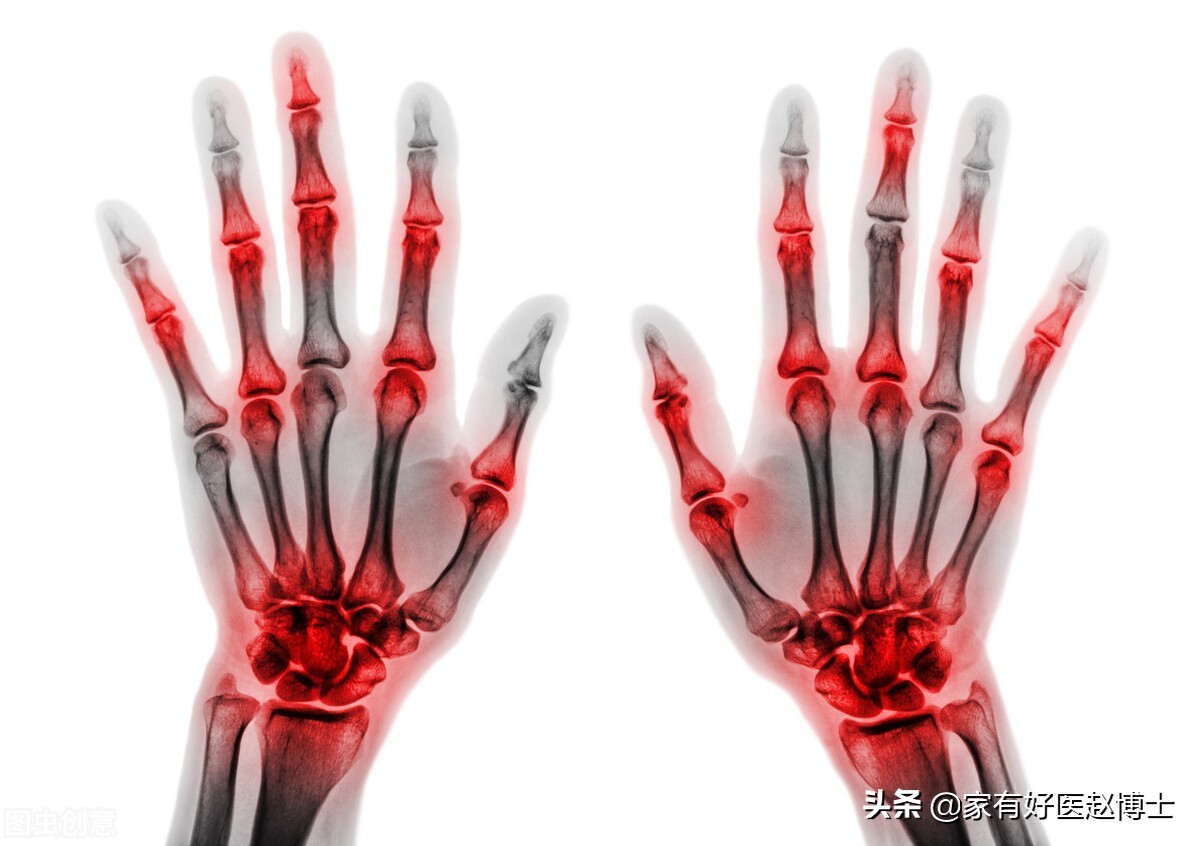

一说起血液当中尿酸水平升高,很多人会直接联想到痛风。

但事实上,并不是所有高尿酸的人群都会发生痛风。有高尿酸但长期不发作痛风,这被称为“无症状高尿酸”。

而高尿酸究竟何时需要使用降尿酸药物,其实关键就是看有没有痛风发作。

2019版《痛风及高尿酸血症基层诊疗指南》告诉我们,有两种情况建议直接启动降尿酸药物治疗:

第一, 是每年痛风(痛风性关节炎)的发作次数≥2次;

第二, 是每年痛风(痛风性关节炎)只发作1次,但是检查发现有明显的痛风石、泌尿系统结石又或者慢性肾脏疾病已达3期以上。